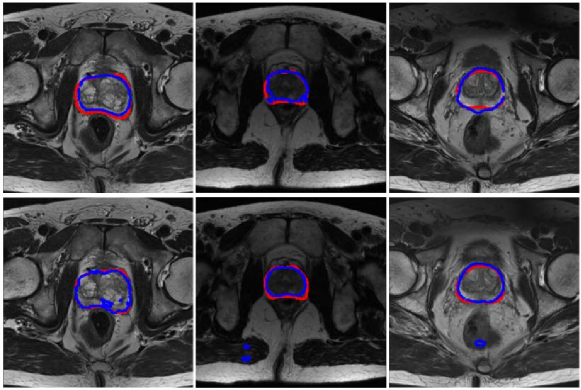

Refer to caption

Figure 2: Top row: Segmentation results of U-Net without long skip connections, which is in fact equivalent to the original FCN; Bottom row: Segmentation results of U-Net. The red and blue contours indicate the ground truth and segmentation results, respectively.

To answer this question, we analyzed the behavior of the classical U-Net ronneberger2015u with and without the long skip connections on the task of prostate segmentation. The segmentation results are shown in Fig. 2. Compared with ground truth segmentation, U-Net can obtain finer details and higher accuracy in general. However, the segmentation result of fully convolutional network (FCN) long2015fully is smoother and that of U-Net picks up non-prostate regions when those areas are highly inhomogeneous. To make the long skip connections inside the network select the useful information and further improve medical image segmentation performance, in this paper, we propose a novel 3D convolutional network, named SIP-Net. Our proposed SIP-Net adopts Densely-connected Residual Blocks (DRBs) and Attention-focused Modules (AMs). The contributions of this work are summarized as follows.